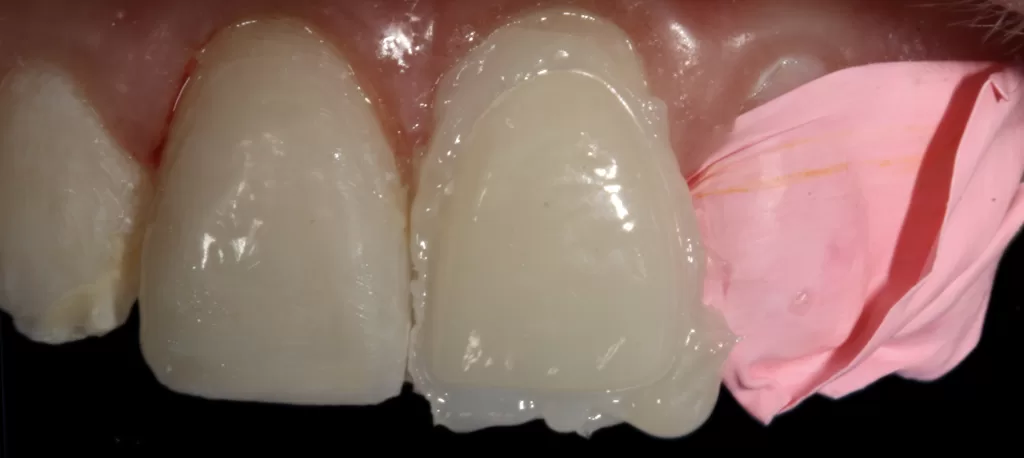

Figures 7a-7c: Uveneer right central labial build-up with packable composite.

- While uncured Uveneer Extra template with G-aenial Injectable Bleach White (GC, Bunkyo-ku, Tokyo, Japan) is pressed as the final layer (aligning the vertical groove on the Uveneer with the long axis of the tooth) and light cured (Figs 7a-7c). Repeat steps 6-11 for the adjacent veneered teeth (Fig 8a).

Once the palatal aspect has been established using the Paladex, the facial is built using a first layer of packable composite that is light cured followed by a second packable composite layer pressed with the Uveneer and left uncured. The Uveneer is then lined with high filler flowable composite (Figs 7a-7c, 8a-8c & 14), pressed onto the uncured second layer of packable composite and cured together; reproducing the aesthetically natural facial anatomy based on Dr. Jan Hajtó’s natural ‘Anteriores’.13